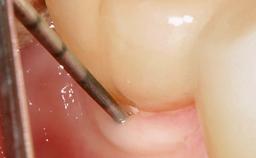

Due to their promising clinical performance, zirconia implants have recently become popular alternatives to titanium implants, particularly for areas with high esthetic demands (Holländer and coworkers 2016; Roehling and coworkers 2016; Lorenz and coworkers 2019). However, regardless of the reported high survival and success rates, zirconia implants were affected by peri-implant diseases over the short observation period, suggesting the importance of treating peri-implant diseases at zirconia implants (Becker and coworkers 2017). In their case, Frank Schwarz and Ausra Ramanauskaite present 3-year results following mechanical debridement alongside Er:YAG laser monotherapy.